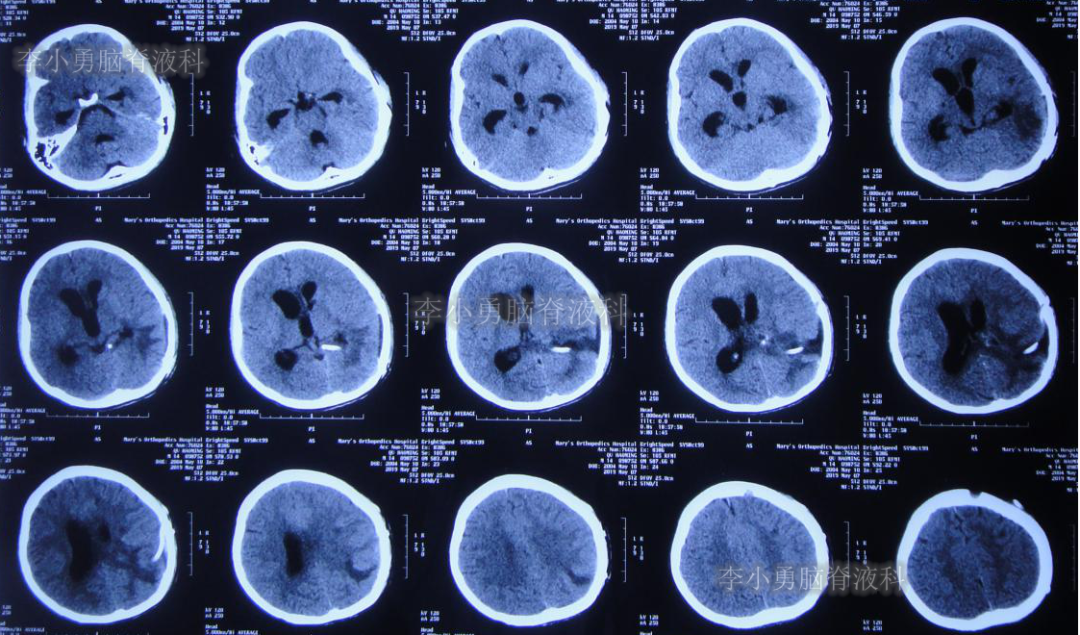

左侧颞角引流术后20天即2019年7月17日,复查头颅CT(图-21):左侧颞角积水消失,水肿消退;患者记忆力也逐渐好转。

图-21:2019年7月17日头颅CT:左侧颞角积水消失,水肿消退

左侧颞角引流术后33天即2019年8月1日,给予试夹闭右侧脑室外引流管,闭管前复查头颅CT(图-22)。

图-22:2019年8月1日夹闭前复查头颅CT

闭管40天后即2019年9月9日复查头颅CT(图-23):脑室仍无扩大。给予拔除右侧脑室外引流管并行左侧颞角-腹腔分流术。

图-23:2019年9月9日头颅CT:拔除右侧脑室外引流管后复查

出院后2个月即2019年12月9日,复查头颅CT示脑室系统较出院时无明显变化(图-25);但患者记忆力仍差。

图-25:2019年12月9日头颅CT

出院后9个月即2020年7月6日,再次复查头颅CT(图-26):未见异常。家属叙述:肢体活动正常,记忆力较前有些改善但较同龄人仍差,已重返校园(图-27)。

图-26:2020年7月6日头颅CT:未见异常